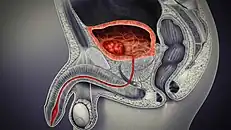

Cancer

Cancer of the bladder is known as bladder cancer. It is usually due to cancer of the urothelium, the cells that line the surface of the bladder. Bladder cancer is more common after the age of 40, and more common in men than women;[33] other risk factors include smoking and exposure to dyes such as aromatic amines and aldehydes.[33] When cancer is present, the most common symptom in an affected person is blood in the urine; a physical medical examination may be otherwise normal, except in late disease.[33] Bladder cancer is most often due to cancer of the cells lining the ureter, called transitional cell carcinoma, although it can more rarely occur as a squamous cell carcinoma if the type of cells lining the urethra have changed due to chronic inflammation, such as due to stones or schistosomiasis.[33]

Investigations performed usually include collecting a sample of urine for an inspection for malignant cells under a microscope, called cytology, as well as medical imaging by a CT urogram or ultrasound.[33] If a concerning lesion is seen, a flexible camera may be inserted into the bladder, called cystoscopy, in order to view the lesion and take a biopsy, and a CT scan will be performed of other body parts (a CT scan of the chest, abdomen and pelvis) to look for additional metastatic lesions.[33]

Treatment depends on the cancer's stage. Cancer present only in the bladder may be removed surgically via cystoscopy; an injection of the chemotherapeutic mitomycin C may be performed at the same time.[33] Cancers that are high grade may be treated with an injection of the BCG vaccine into the bladder wall, and may require surgical removal if it does not resolve.[33] Cancer that is invading through the bladder wall may be managed by complete surgical removal of the bladder (radical cystectomy), with the ureters diverted into a segment of part of ileum connected to a stoma bag on the skin.[33] Prognosis can vary markedly depending on the cancer's stage and grade, with a better prognosis associated with tumours found only in the bladder, that are low grade, that do not invade through the bladder wall, and that is papillary in visual appearance.[33]